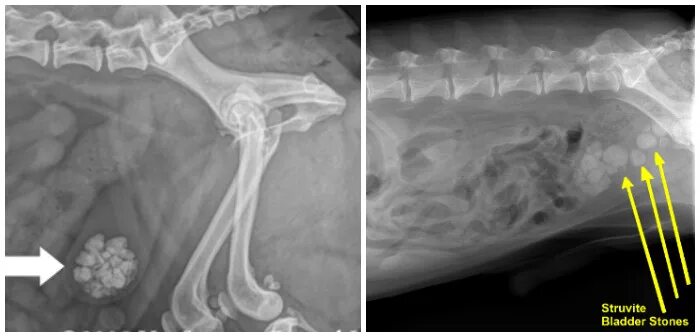

Уретры мкб